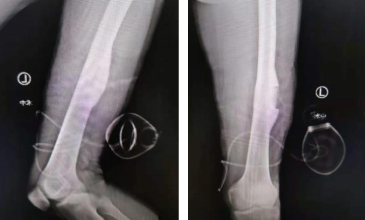

手术当天,郑主任手术团队在3D扫描下完成对股骨病灶的三维影像建立,郑主任操作天玑骨科机器人,实现病灶的精确定位,凭借导航指引,微创、精准切除瘤巢。经测量,瘤巢大小约0.8cm× 0.5cm。肿瘤切除后患者原有的疼痛症状消失。

术中切除的瘤巢及部分骨质

术后